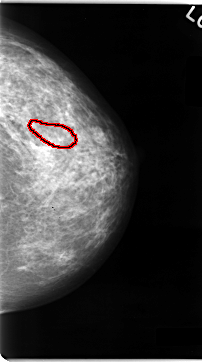

ics_version 1.0 filename C-0060-1 DATE_OF_STUDY 11 3 1993 PATIENT_AGE 47 FILM FILM_TYPE REGULAR DENSITY 3 DATE_DIGITIZED 23 10 1997 DIGITIZER LUMISYS LASER SEQUENCE LEFT_CC LINES 4704 PIXELS_PER_LINE 2624 BITS_PER_PIXEL 12 RESOLUTION 50 OVERLAY LEFT_MLO LINES 4704 PIXELS_PER_LINE 2512 BITS_PER_PIXEL 12 RESOLUTION 50 OVERLAY RIGHT_CC LINES 4704 PIXELS_PER_LINE 2696 BITS_PER_PIXEL 12 RESOLUTION 50 OVERLAY RIGHT_MLO LINES 4712 PIXELS_PER_LINE 2672 BITS_PER_PIXEL 12 RESOLUTION 50 OVERLAY |

FILE: C_0060_1.LEFT_MLO.OVERLAY TOTAL_ABNORMALITIES 1 ABNORMALITY 1 LESION_TYPE CALCIFICATION TYPE AMORPHOUS DISTRIBUTION CLUSTERED ASSESSMENT 4 SUBTLETY 2 PATHOLOGY MALIGNANT TOTAL_OUTLINES 1 BOUNDARY |